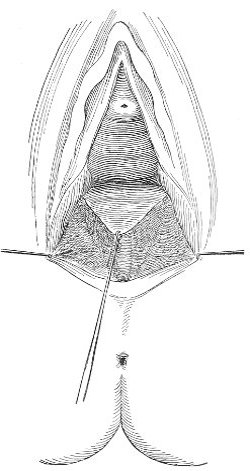

Slight Median laceration of the Perineum.—In this injury the tear takes place through the fourchette. Posteriorly it may extend as far as the sphincter ani muscle. Upward it may extend for an inch up the posterior vaginal wall. The appearance of this tear is shown in Fig. 33. It will be noted that, as this tear takes place in the median line, none of the muscles that support the perineum are involved, nor are the planes of fascia injured. The perineum is slightly split, and the insertions and origins of the muscles and the fascia are slightly separated. The supporting structures of the perineum and the pelvic floor are, however, uninjured.

Fig. 33.—Recent slight median laceration of the perineum: sutures introduced.

If this tear is detected after labor, it should be closed by the immediate operation. A slight tear involving chiefly the cutaneous aspect of the perineum should be closed by three or four sutures introduced from the outside, as in Fig. 33. The needle should be introduced about a quarter of an inch from the edge of the wound. It should not be passed parallel with the plane of the lacerated surface, but should be swept outward and then inward toward the 68 angle at the bottom of the tear (Fig. 34). It may either emerge at the angle and be re-introduced, or it may be passed directly through to the skin-margin on the opposite side of the wound. If the suture is passed in this way, there will be perfect apposition throughout the whole surface of laceration. If the sutures are improperly passed, there may result only apposition of the skin-edges.

Fig. 34.—Diagram representing the correct and the incorrect method of passing the suture for closure of slight perineal laceration.

If the laceration extends up the posterior vaginal wall, two sets of sutures must be introduced—one on the vaginal aspect of the tear, and one on the skin aspect (Fig. 35).